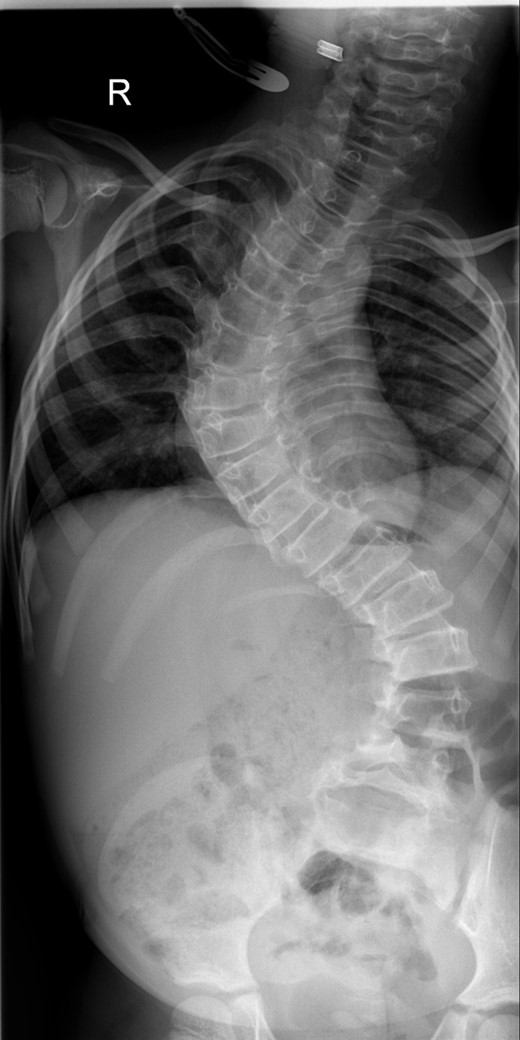

Subsequent transcutaneous, magnetic spinal lengthening has been performed on six occasions in the outpatient setting over the last 2 years. This has been uncomplicated and has not been associated with significant pain or fracture. She takes paracetamol after each magnetic lengthening procedure, easing mild muscular discomfort. The control of the scoliosis has been maintained, and at 2 years post-insertion of MCGR the spinal curves now measure 40° for the thoracic curve and 37° for the thoracolumbar curve with a T1–S1 height of 288 mm and T1–T12 height of 195 mm (Fig. 3). The MCGR have been lengthened by 16 mm on either side.

A whole spine radiograph at age 8 following multiple lengthening procedures showing elongation of the MCGR rods (measuring 40° for the thoracic curve and 37° for the thoracolumbar curve with a T1–S1 height of 288 mm and T1–T12 height of 195 mm).